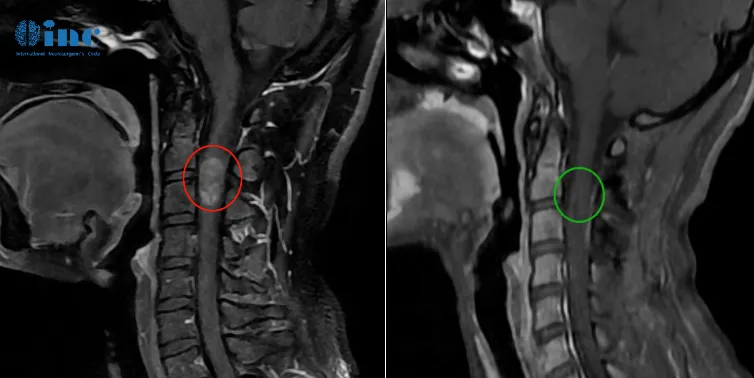

33岁男性-脊髓髓内室管膜瘤

40岁刘先生因为出现持续的脖子肩膀酸痛、手抖、平衡性差、头晕等症状就医检查,诊断为脊髓髓内肿瘤,多地咨询后都因为手术易致残建议不手术,但是不手术,症状只会越演越烈。

▼巴教授术前术后影像对比

巴教授邮件回复:

“目前我会给病人提供手术探查,目的是获得精确诊断的材料。如果病变可以做手术,当然会切除。如果不能,由于各种形态学的原因,这是可能的发生的,那么能做的操作就只能是活检。”

2021年教授疑难示范手术期间,INC巴教授成功为刘先生手术,脊髓髓内肿瘤得到全切,术后病理为脊髓髓内室管膜瘤,室管膜瘤为良性肿瘤,顺利手术,预后良好。